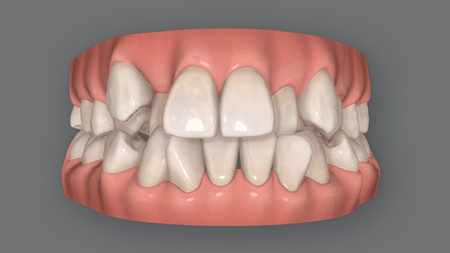

上下顎前突(じょうげがくぜんとつ)とも呼ばれる口ゴボは、上下の前歯が前方に飛び出して見える症状。

また歯がガタガタの叢生乱杭歯)や、八重歯を併発している患者さんも少なくありませんが、こうした症状も口ゴボの矯正で治せます。

口ゴボが改善されると、もともとの小顔が活きた、すっきりとした小顔美人になります。

※効果には個人差があります